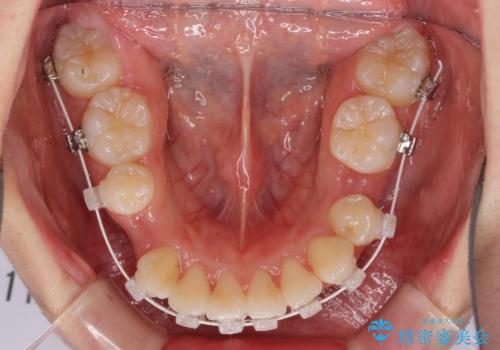

- 矯正装置

- 審美装置

咬み合わせの乱れが著しく、治療途中で一部反対咬合となってしまいました。

アンカーなどをうまく使用して、3年の期間を要してきれいに仕上げることができました。